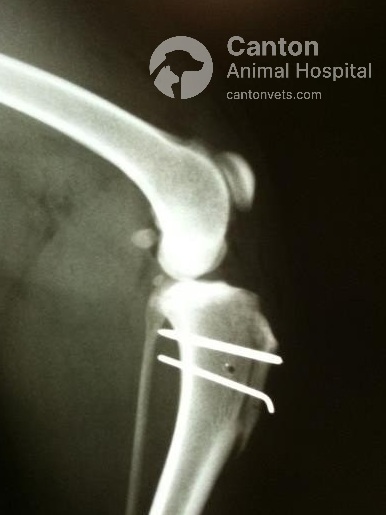

1. Tibial Tuberosity Transposition (TTT)

The tibial tuberosity, where the patellar tendon attaches, is surgically repositioned to correct patellar alignment.

A small bone fragment is cut, shifted, and secured with pins or screws to lower the kneecap’s resting position.